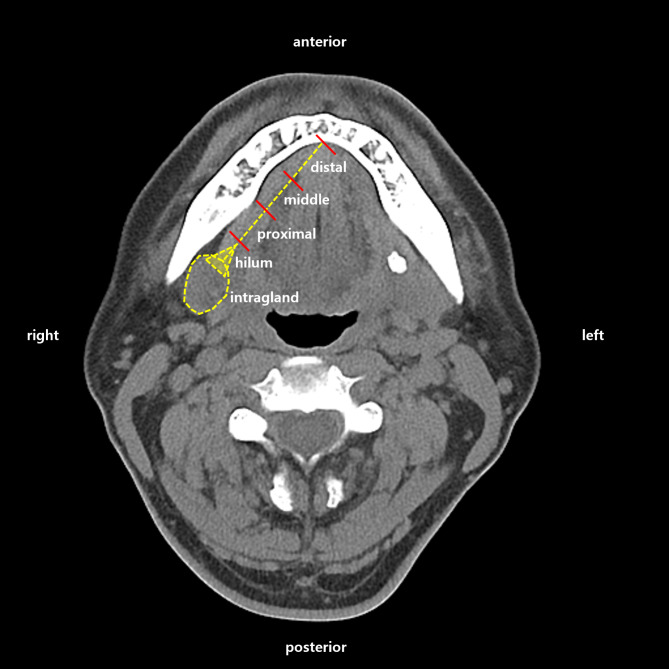

Methods: We performed a retrospective review of the medical records of patients who underwent intraoral stone removal between 2006 and 2022. Two different surgical approaches were applied based on the stone location as determined by preoperative CT scans. The mediolingual approach was used for superficial stones, while the laterogingival approach was reserved for deeper stones. Patient demographics, sialolithiasis features, and postoperative complications were analyzed. T-test was performed to compare stone characteristics between different locations, and a receiver operating characteristic curve analysis was used to identify the critical size threshold for predicting stone location.

Results: Medical records of 465 patients were reviewed. Out of 616 stones, 614 were successfully removed with two distinct surgical approaches guided by preoperative CT scans. Two patients reported retention, and 11 experienced postoperative tongue sensation changes. The hilum was the most common stone location, and deeper stones, approached laterolingually, were generally larger. Analysis identified a 4.25 mm width as the most sensitive and specific threshold for deep stones. Stone volume showed no statistically significant difference between smokers and non-smokers, alcohol consumers and non-consumer.